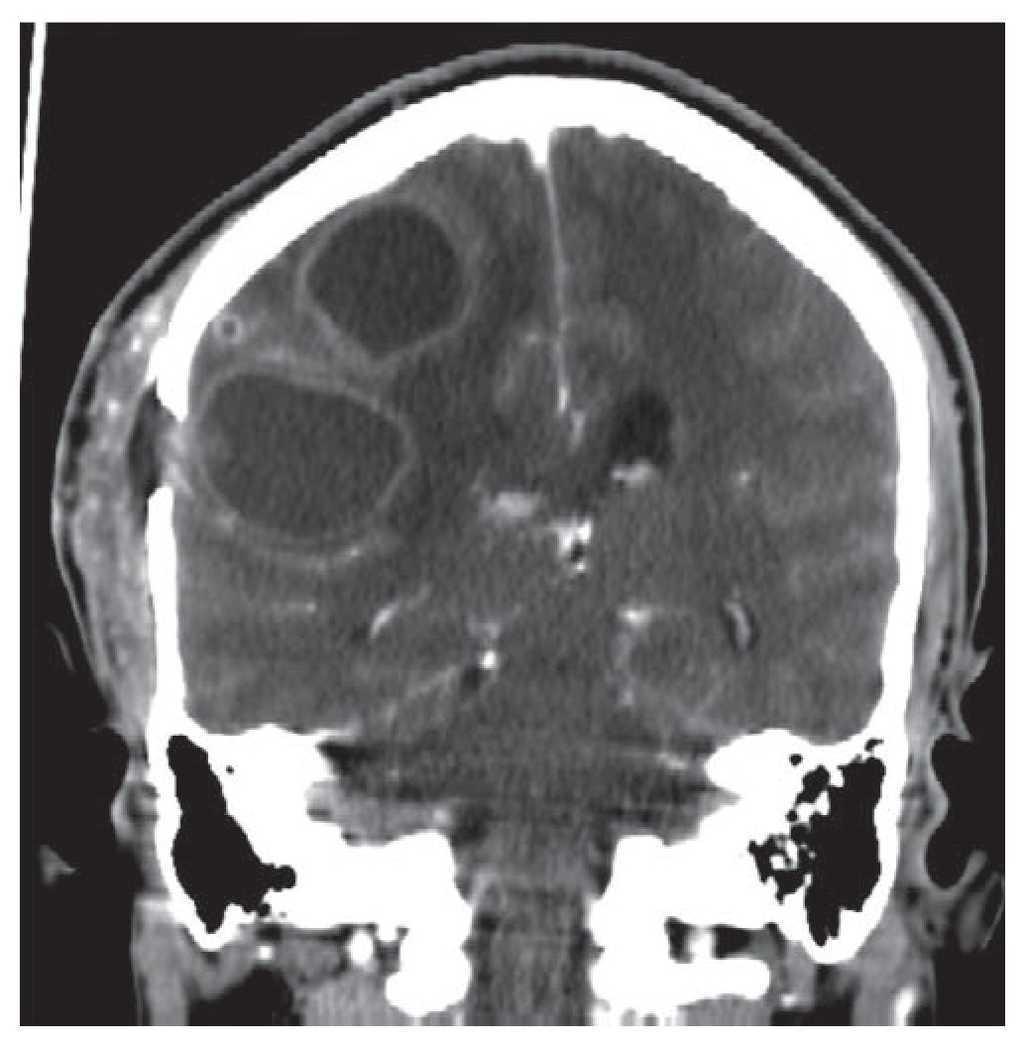

We performed a cranial CT scan with contrast 10 days after surgery, where we were able to see an abscess recurrence and an increment in size to 15 mL (figure 3). The patient remained in the same clinical condition during that period of time. We decided to perform a second surgery consisting of a right parietal burr hole (22 mm) and reopening of the initial right temporal burr hole for abscess needle aspiration, obtaining 15 mL of yellowish green purulent fluid from the parietal burr hole and 12 mL of hematic fluid mixed with dark green purulent fluid from the temporal skull burr hole.

Figure 3 Contrasted coronal computerized tomography scan with bilobed recurrent abscess.